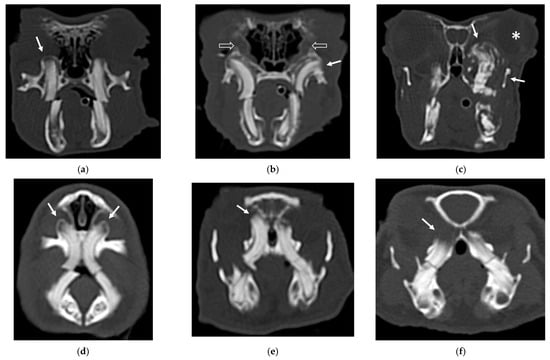

An example of the three categories of secondary bone lesions is shown for a rabbit and a guinea pig in Figure 2.

Figure 2.

Transverse CT images of mandibular secondary bone lesions of three rabbits (a–c) and three guinea pigs (d–f) included in the study; bone algorithm. (a,d) Bulging around tooth without focal lysis (white arrows); (b,e) bulging around tooth with focal lysis (white arrow); (c,f) aggressive bone lesion associated with teeth (white arrow). Note the associated cavernous occupying lesion of soft tissues (white asterisk) in image (c).

The IT were more frequently involved in guinea pigs with aggressive bone lesions associated with teeth (3). In the second group of patients, variable involvement of different groups of teeth was observed. The involvement of the premolar and molar teeth presented variable distribution in both species in all three categories of secondary bone lesions. Only three rabbits and three guinea pigs exhibited involvement of IPMT, associated with aggressive bone lesion associated with teeth (3) in rabbits, and bulging around tooth root with focal lysis (2) and aggressive bone lesion associated with teeth (3) in guinea pigs, respectively, in two and one patients.